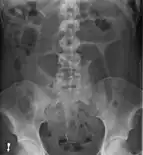

After taking a thorough history, the diagnosis of colonic volvulus is usually easily included in the differential diagnosis. Abdominal plain x-rays are commonly confirmatory for a volvulus, especially if a "bent inner tube" sign or a "coffee bean" sign are seen. These refer to the shape of the air-filled closed loop of colon which forms the volvulus. Should the diagnosis be in doubt, a barium enema may be used to demonstrate a "bird's beak" at the point where the segment of proximal bowel and distal bowel rotate to form the volvulus.

Volvulus with gangrene of the sigmoid